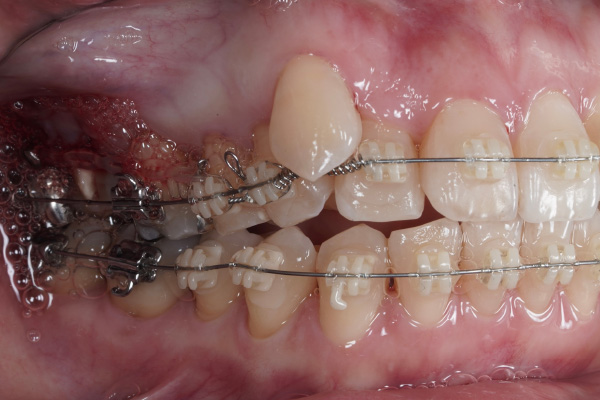

ワイヤー矯正でどこが変わる?

矯正治療では、歯を動かす「力」を計画的にかけることで、

⚫︎八重歯の位置

⚫︎前歯の咬み合わせ

⚫︎歯列全体のバランスが少しずつ改善していきます。

この症例の場合も、4ヶ月→8ヶ月で目に見える変化がありました。

歯の動きはゆっくりだけど確実

年齢が上でも、骨や歯周組織の状態が良ければ動きは着実です。